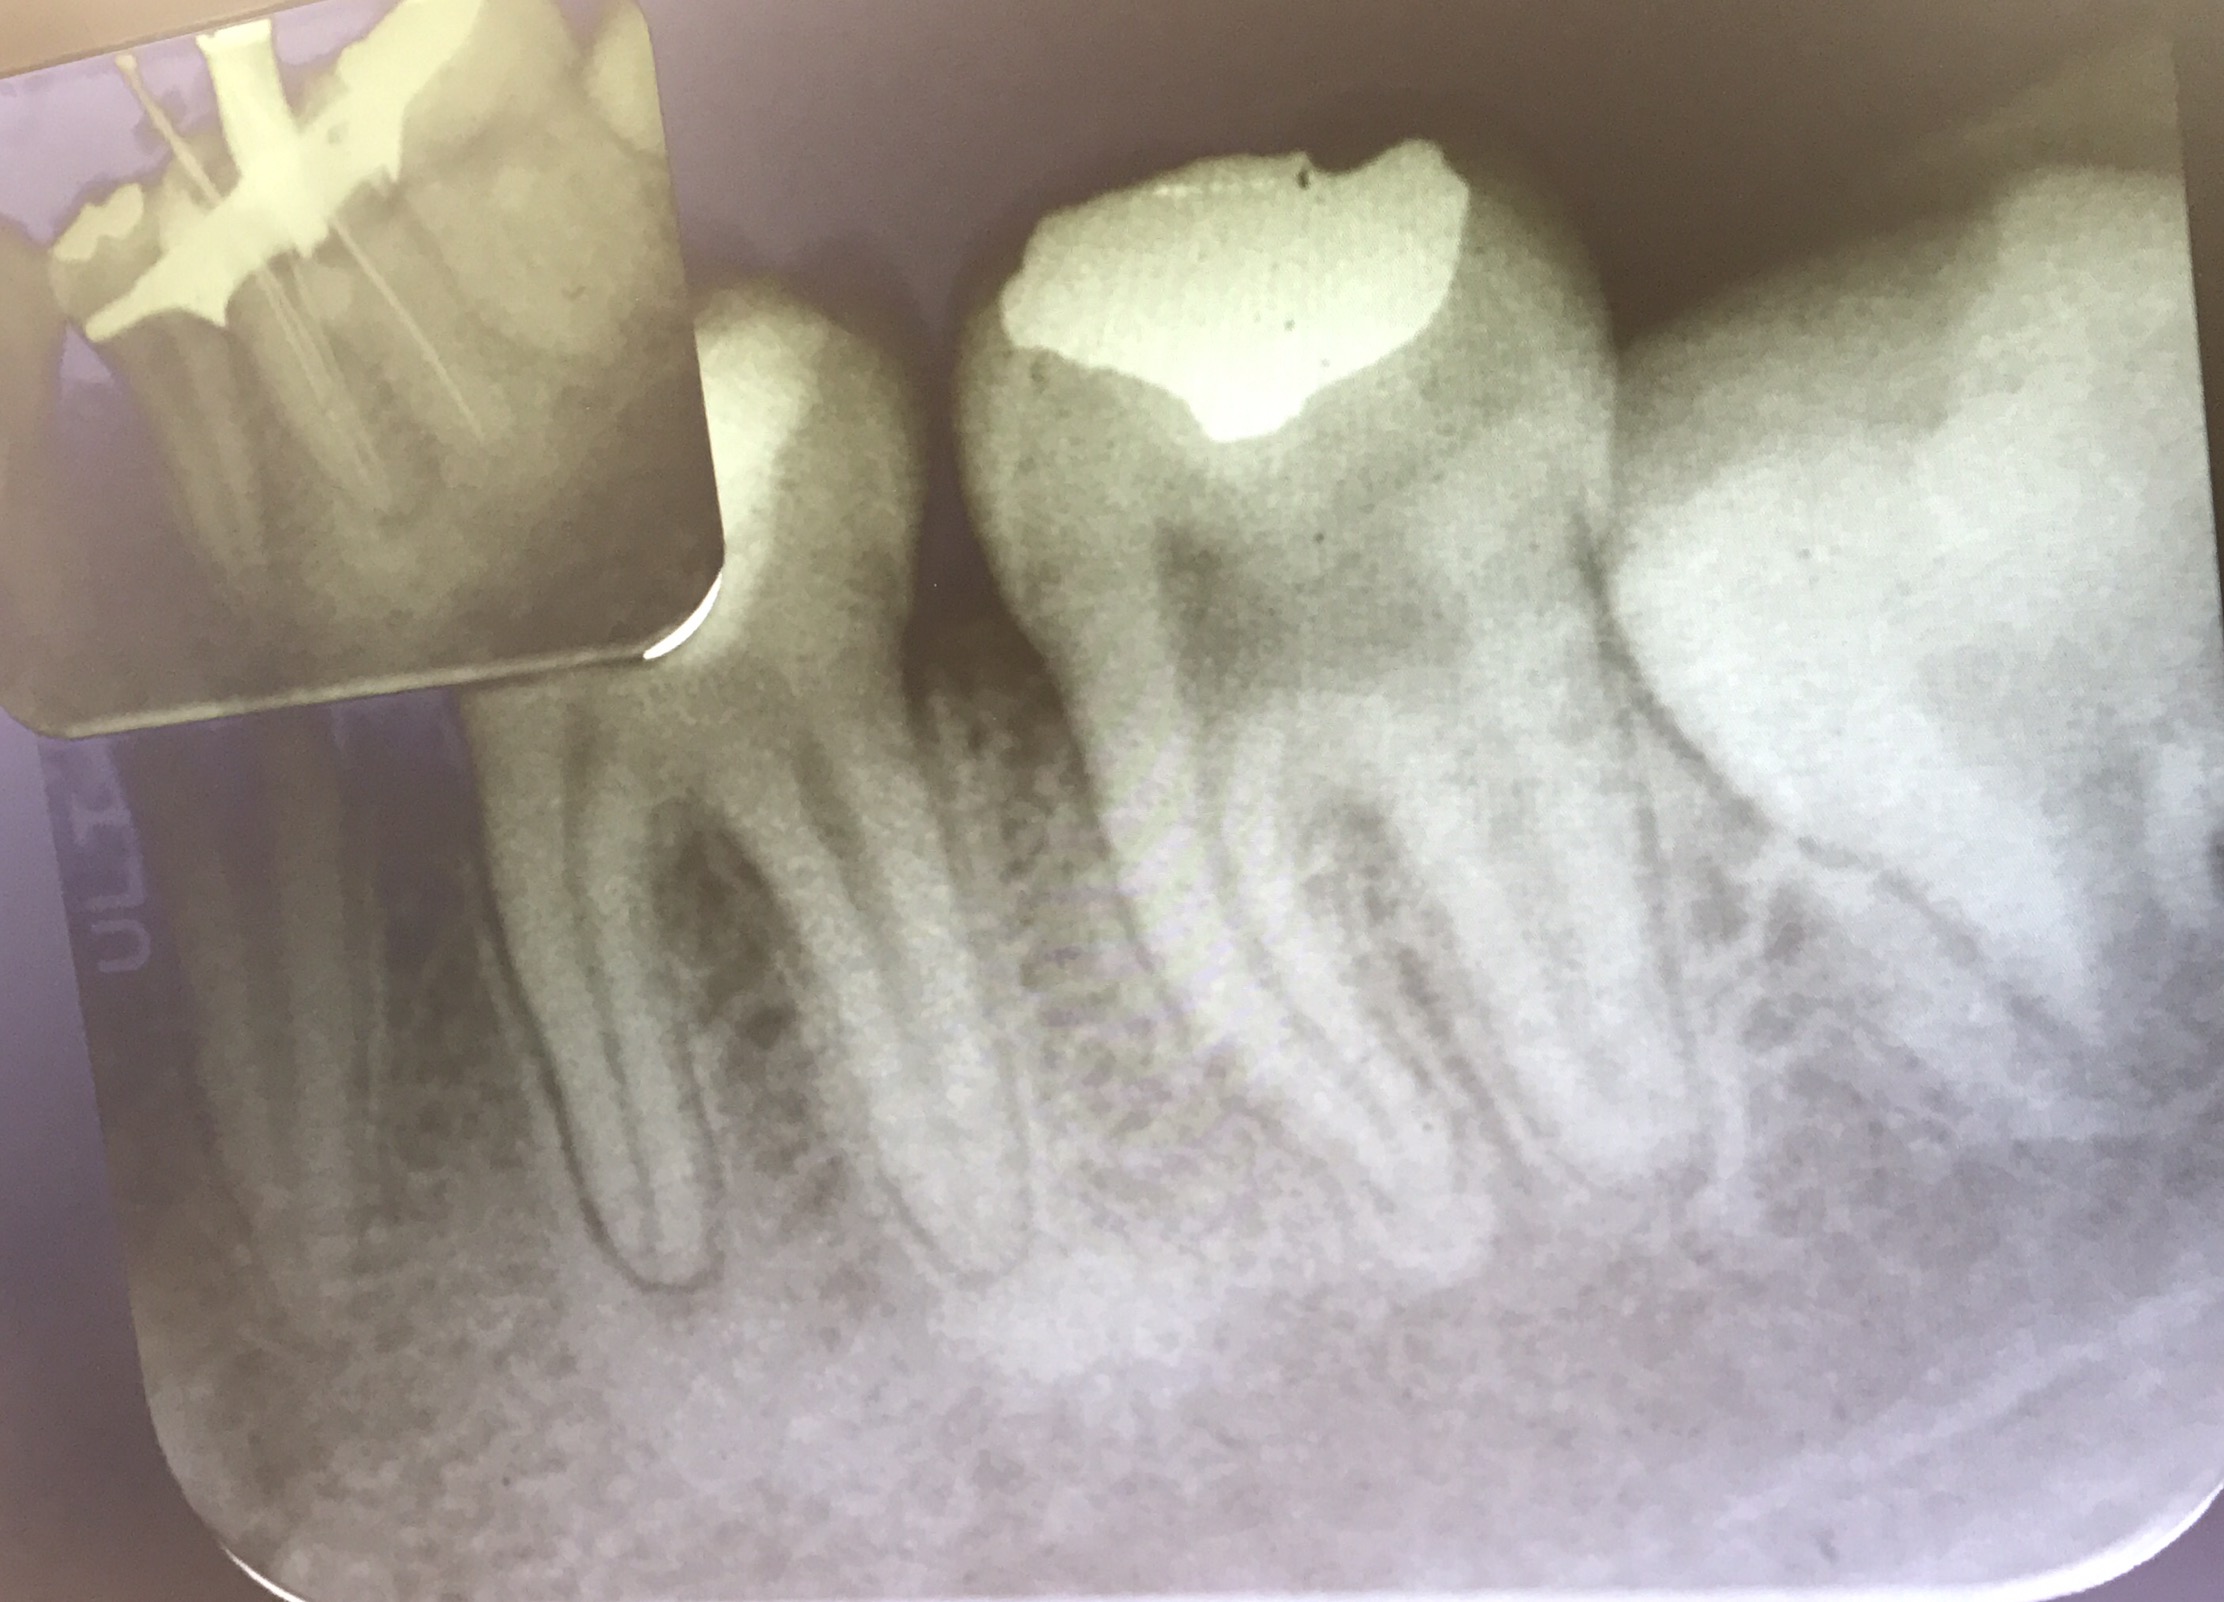

case แสดง Root canal retreatment ฟันซี่นี้มี Post หักที่ Distal root

การ Dx เช่น Apex locator ร้องก่อนถึง WL , ลักษณะเหงือกบริเวณใกล้ปลายรากจะปกติ แต่บริเวณ crestal bone จะแย่ลง เป็นต้น

อันนี้คือ case จริงครับ ส่วนที่ Outline ไว้ตรงกลางคือ รอย Perforate